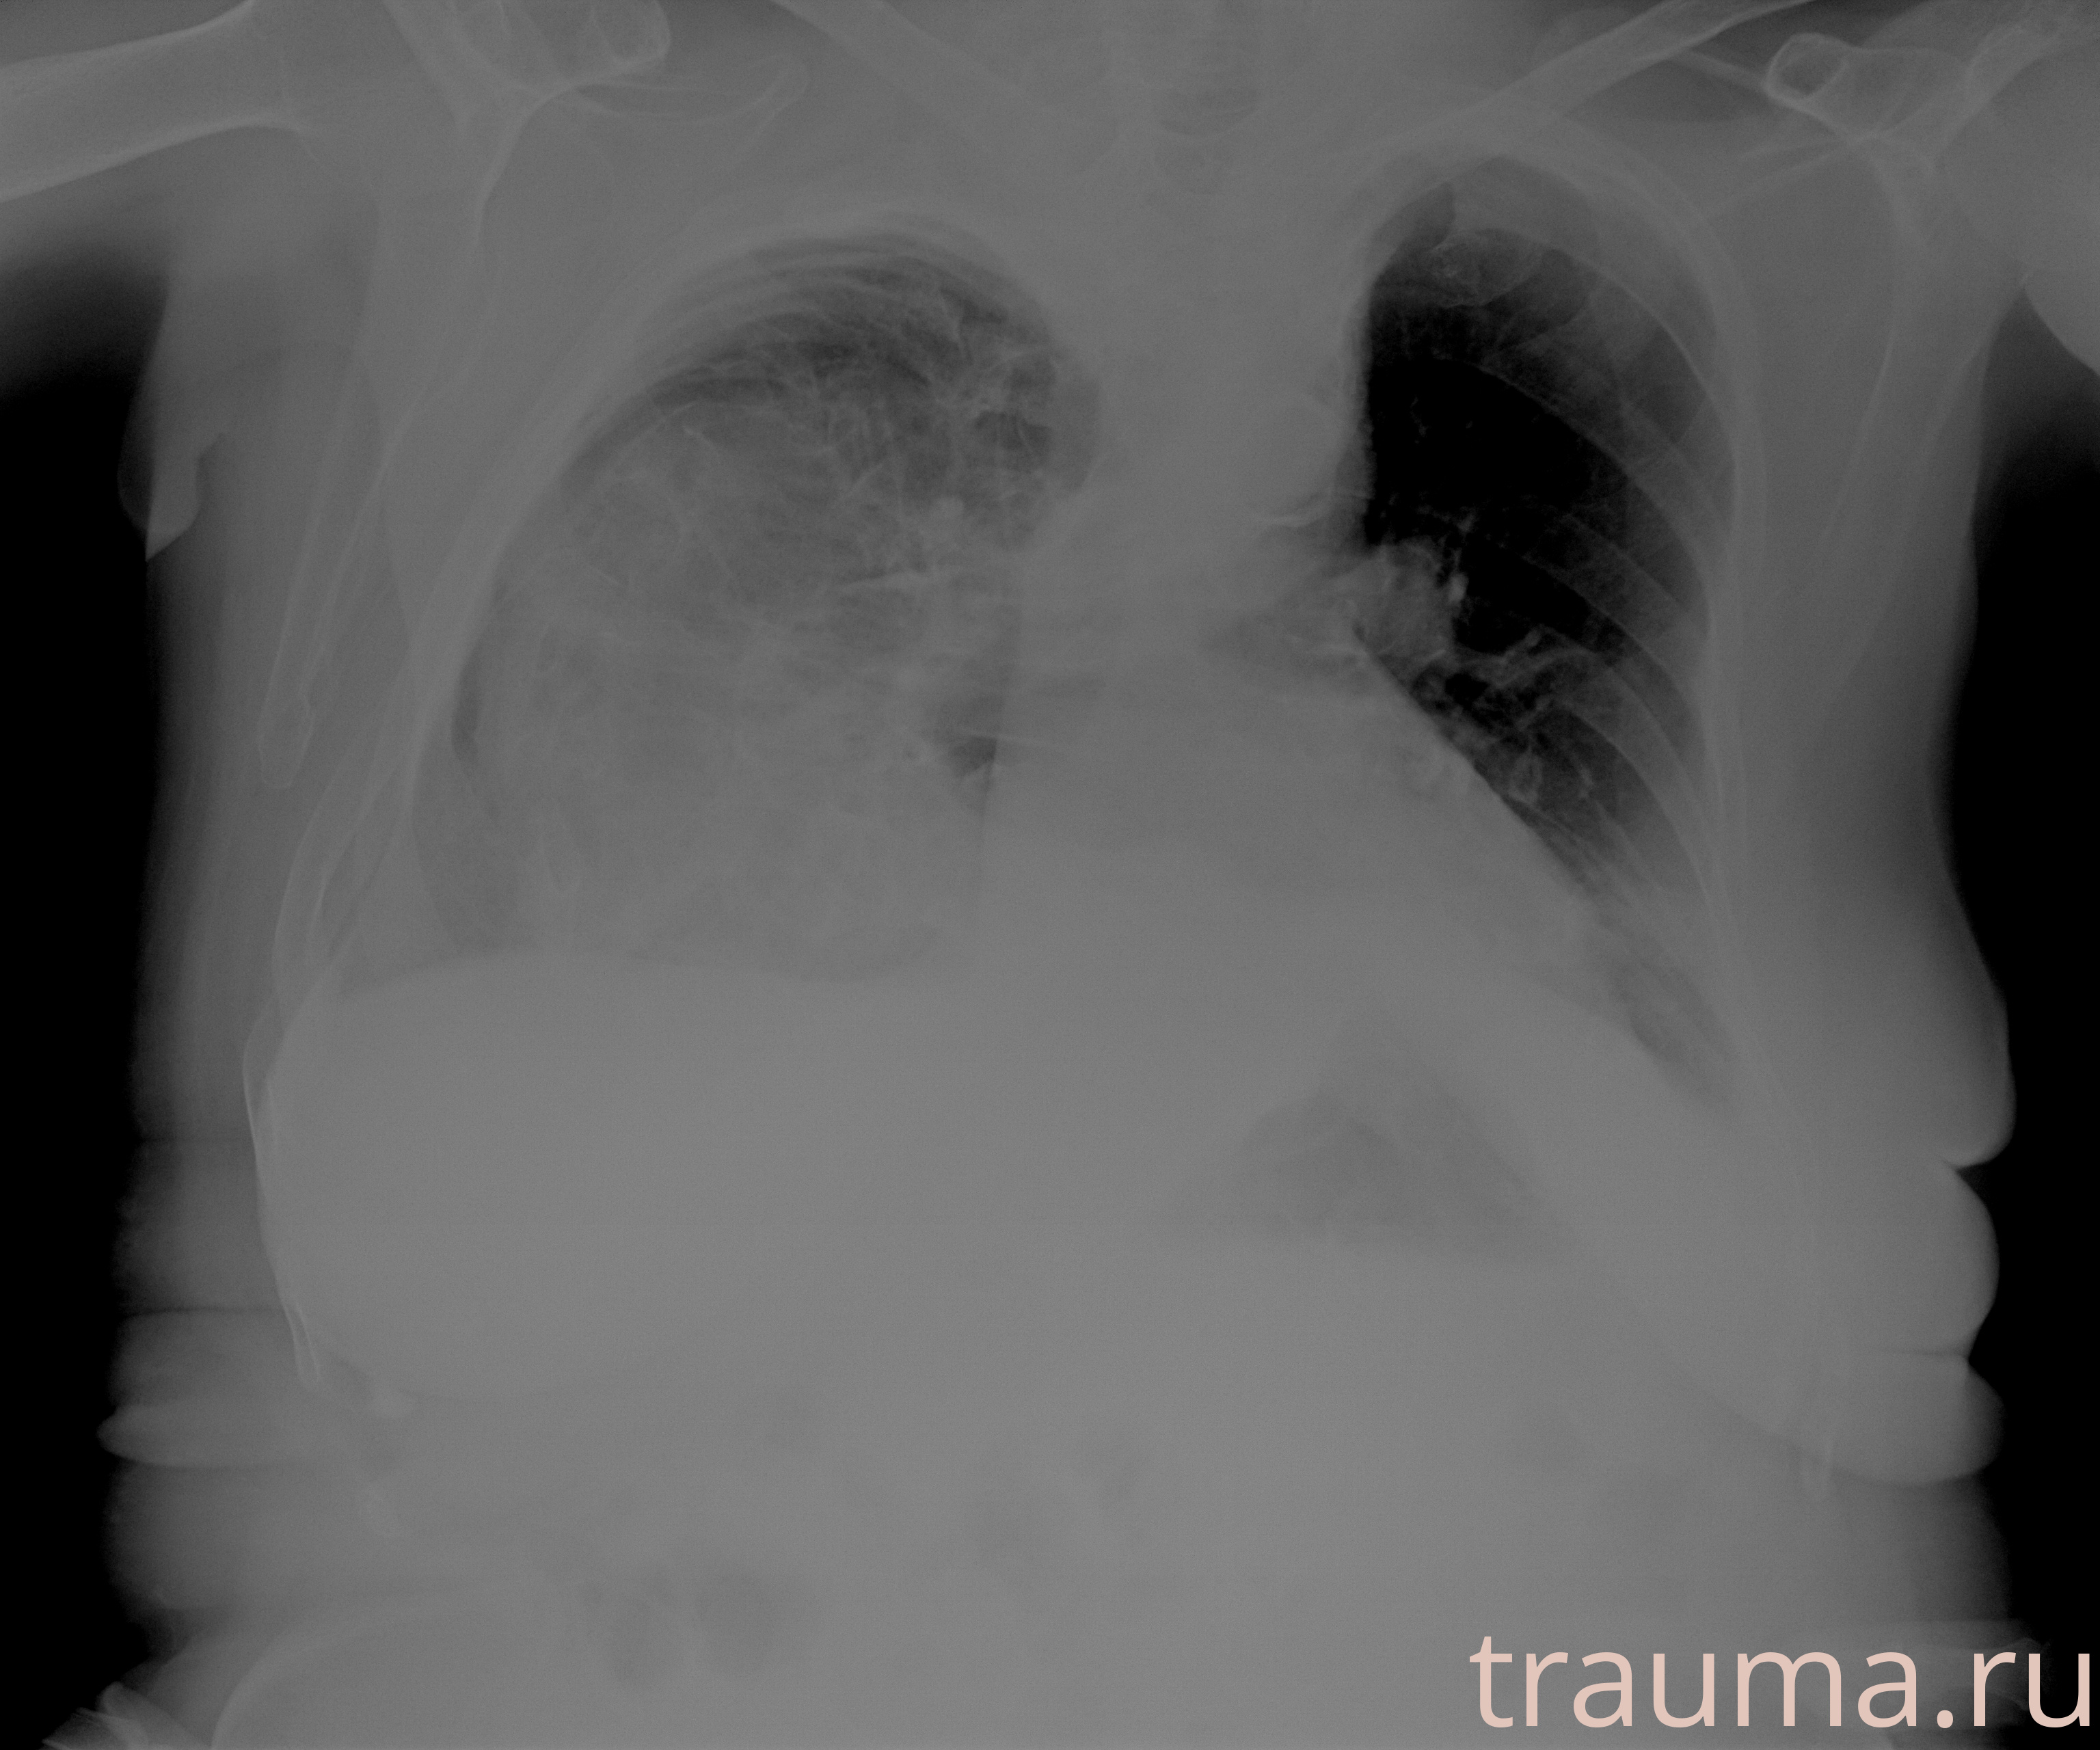

Рентгенограммы

Рентген на дому: по вашему адресу приезжает врач-рентгенолог, травматолог-ортопед с мобильным рентгеновским аппаратом, проводит диагностику травмы или заболевания, делает необходимые рентгенограммы, дает рекомендации по дальнейшему лечению. Получить качественные снимки в домашних условиях возможно благодаря уникальной методике, разработанной МосРентген Центром для института  Склифосовского

при переломе шейки бедра и пневмонии от компании МосРентген Центр - партнера Института имени Склифосовского